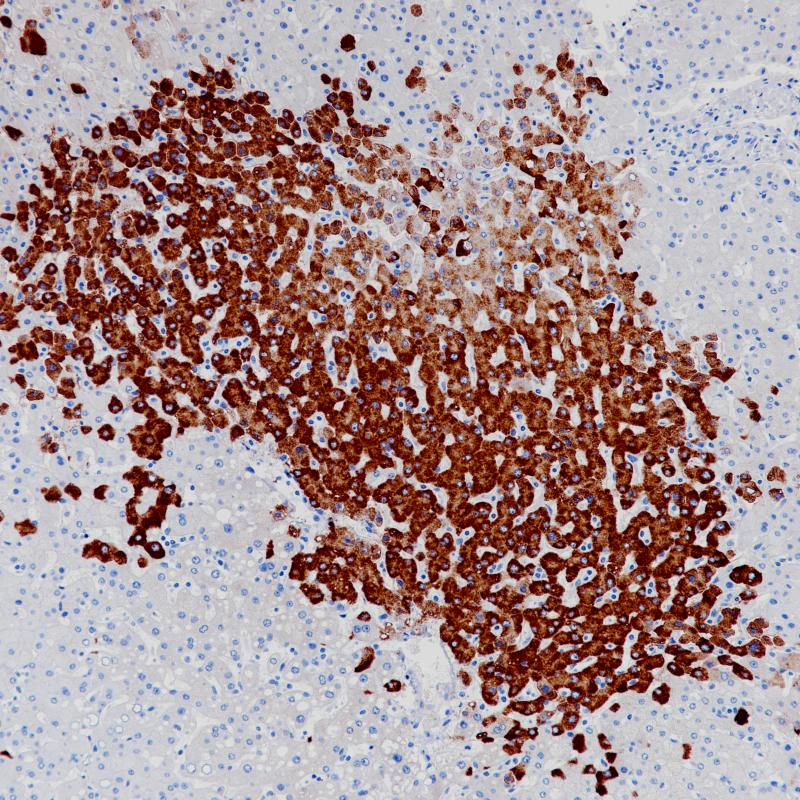

HBV感染肝脏HBSAg(BP6224)染色

乙肝表面抗原(HBsAg)是乙肝病毒表面的糖蛋白。乙肝感染后,HBsAg作为第一病毒标志物出现。患者感染乙型肝炎病毒2到6个月后,HBsAg可以在其血液、唾液、乳汁,汗水,泪水,鼻咽分泌物、精液和阴道分泌物中检测到。HBsAg抗体主要用于乙肝病毒的诊断。

阳性对照

HBV感染肝脏

亚细胞定位

细胞质